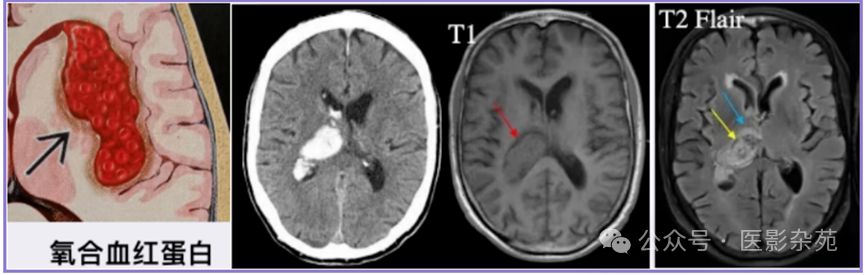

细胞内氧合血红蛋白

T1:等信号

T2:等信号至高信号

DWI:高

ADC:低